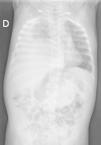

The workup was completed with ultrasound and CT scans that evinced the presence of right diaphragmatic hernia (RDH) with incarceration of the right lobe (RL) of the liver and ascites, dilation of the biliary tract and collapse of the hepatic veins and suprarenal inferior vena cava with collateral venous circulation (Fig. 2).